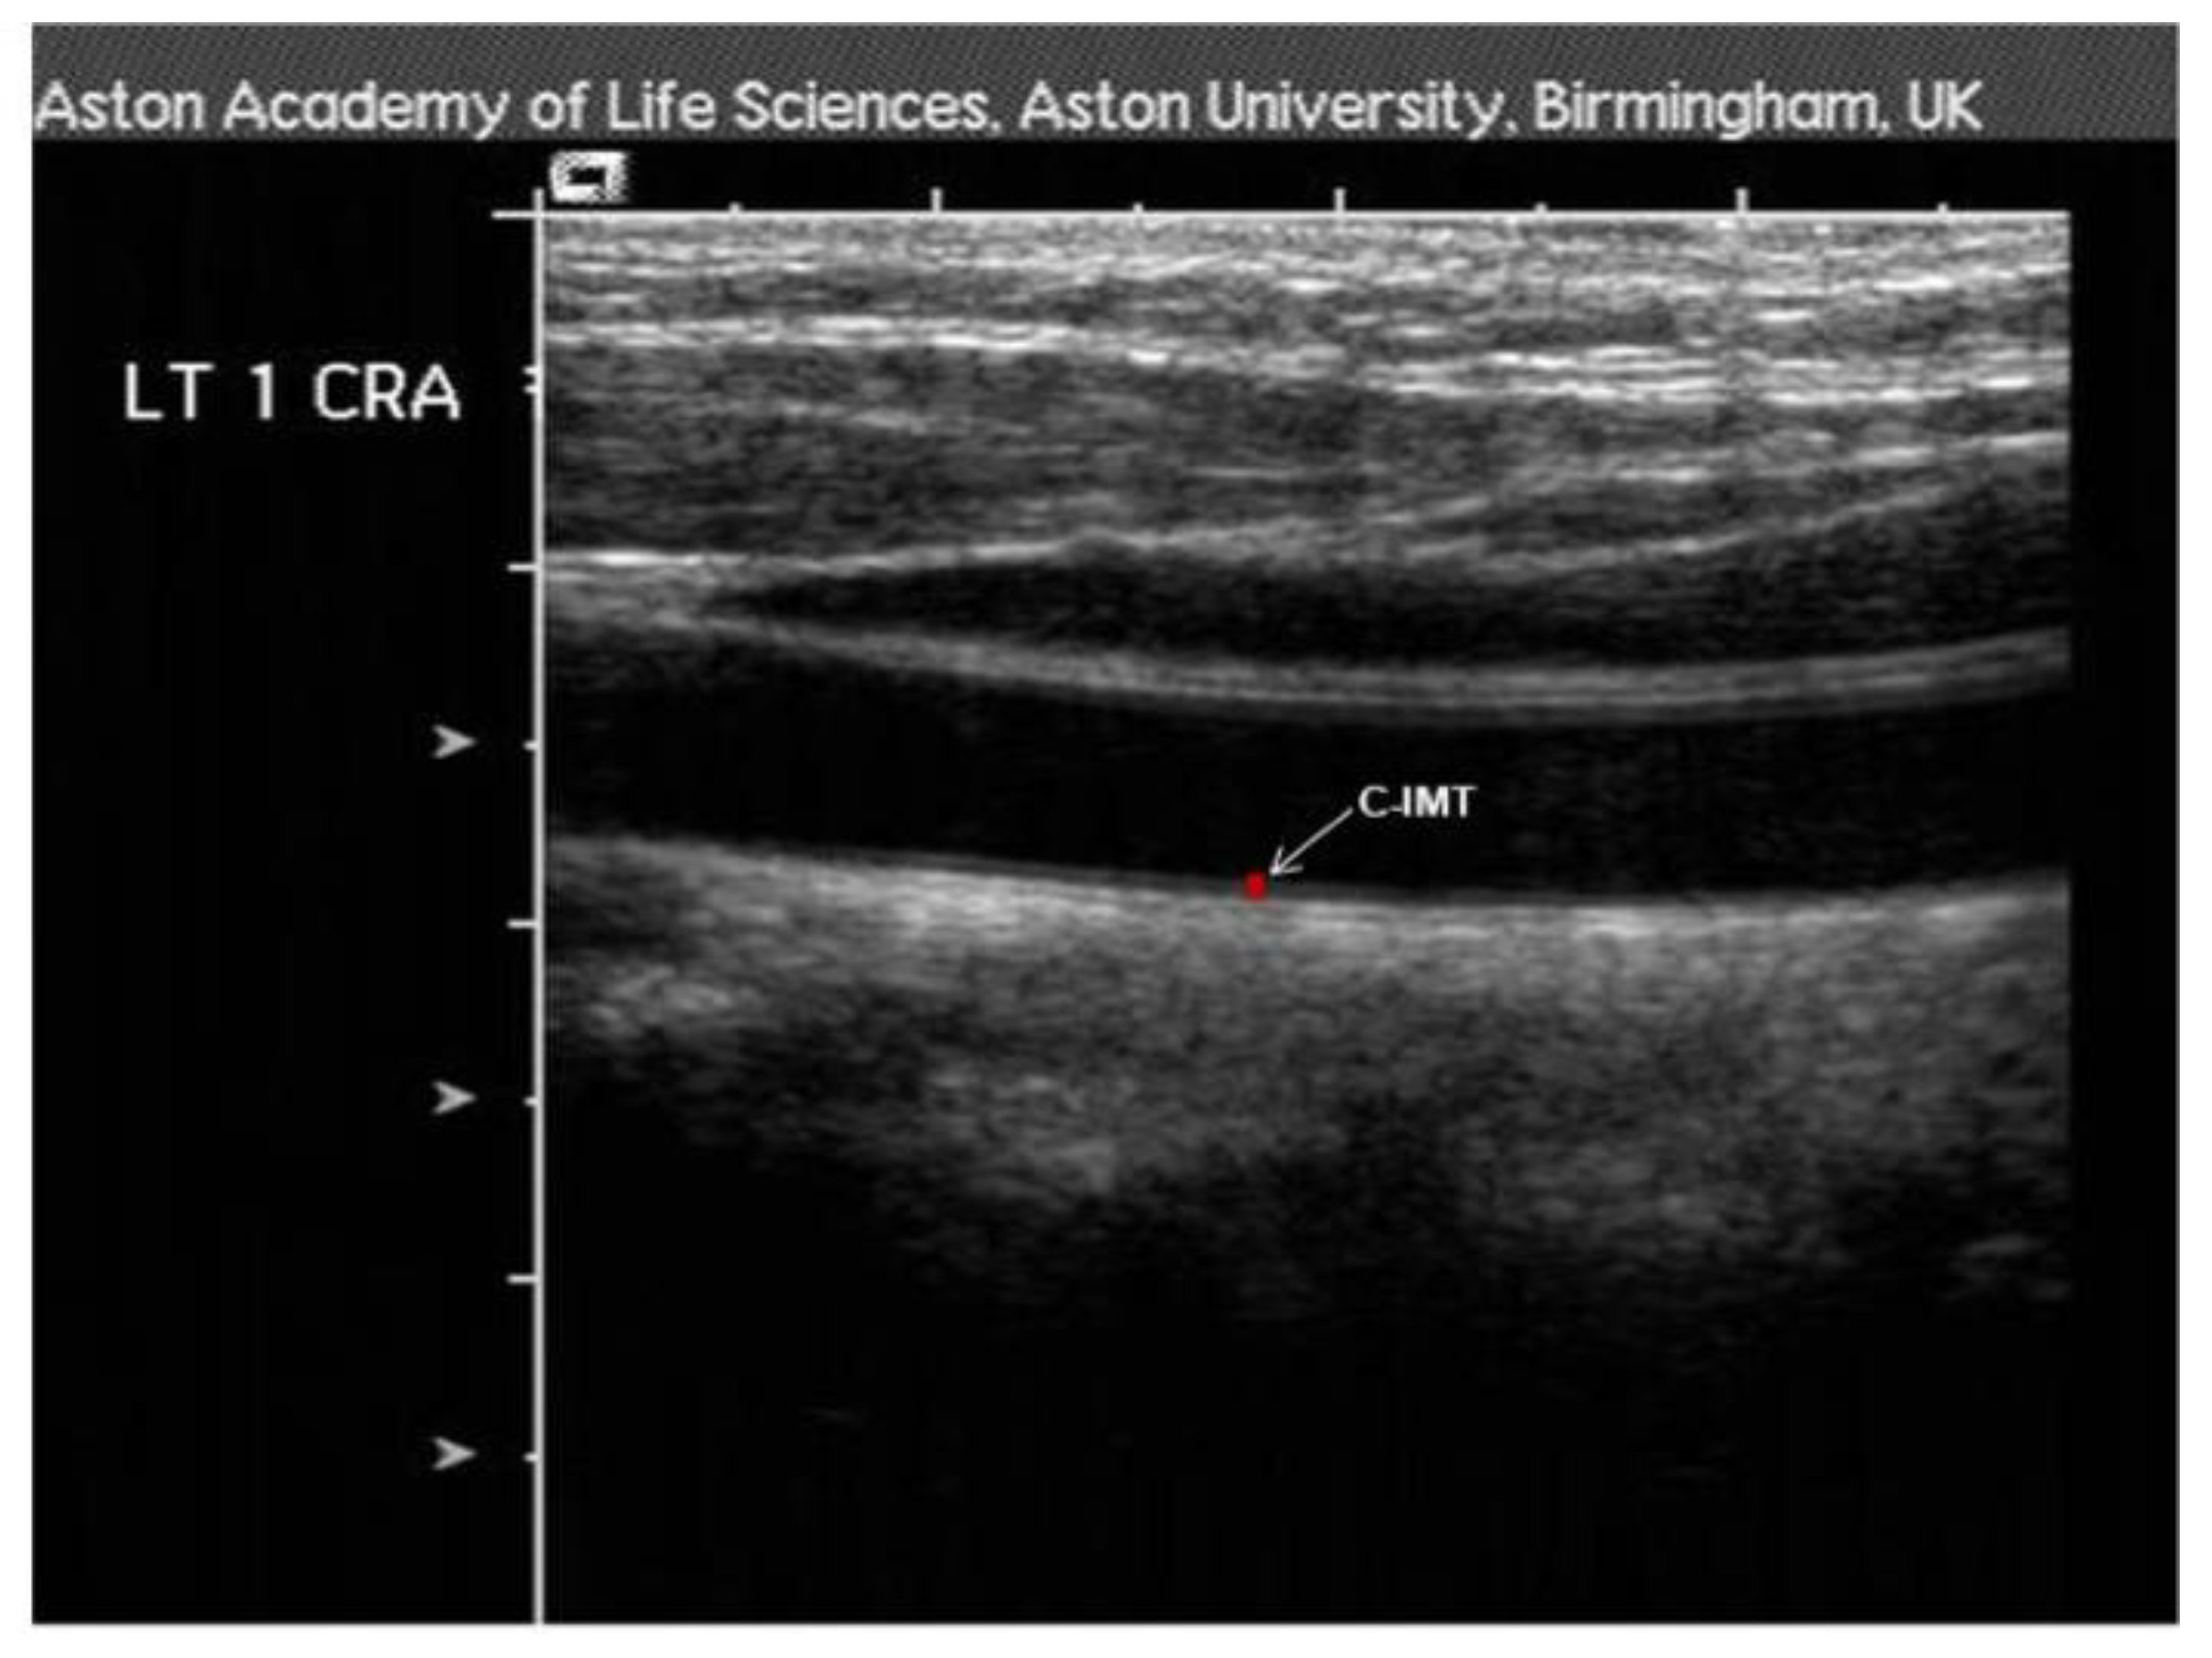

2.8.3. Carotid-Intima-Media Thickness (c-IMT)

| c-IMT | |||

| R-IMT (cm) | 0.75 (0.15) | 0.70 (0.11) | 0.300 |

| L-IMT (cm) | |||